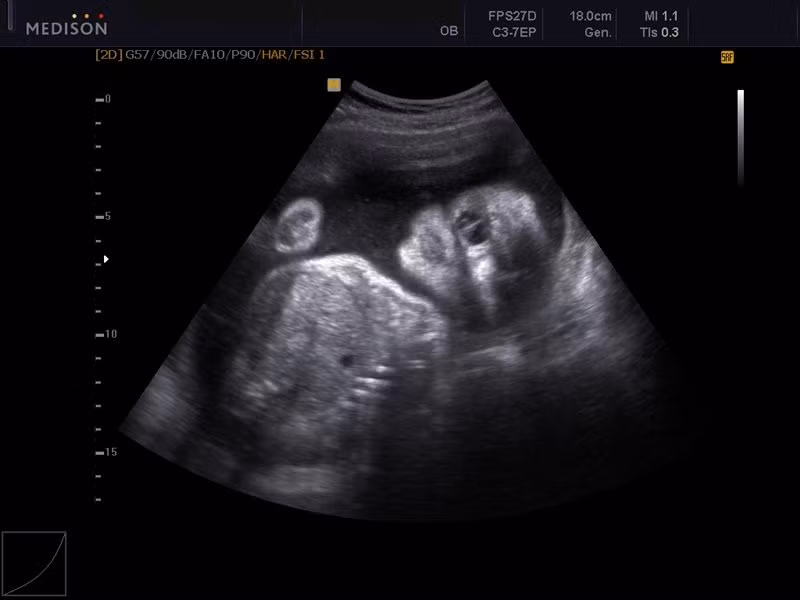

Hội chứng được đặt tên theo những quái vật thần thoại Hy Lạp nổi tiếng Cyclop. Những đứa trẻ chào đời với hội chứng cyclopia có một mắt duy nhất nằm giữa đầu.

Những em bé mắc hội chứng mang tên quái vật thần thoại Hy Lạp này được sinh ra với dị tật một mắt ở giữa trán và không có mũi, miệng.

Vì vậy, hầu hết các trẻ bị Cyclopia không thể thở được bên ngoài dạ con, các em thường qua đời trước hoặc ngay sau khi được sinh ra.

Theo lý giải khoa học, sự dị dạng này bị gây ra bởi thất bại trong quá trình hình thành não trước và khoang mũi. Do đó, hai mắt của người sẽ hình thành một mắt nằm giữa trán hoặc đằng sau đầu.

Những đứa trẻ bị dị tật chỉ có một mắt không thể sống sót vì chúng thường mắc những dị tật khách như tim dị dạng.

Tỷ lệ trẻ mắc dị tật Cyclop là 4/1.000 ca sinh và thường xảy ra phổ biến hơn ở động vật. Dù vậy, đã có không ít những ca mắc dị tật hiếm này ở người và được y văn thế giới ghi lại.

Cụ thể ngày 1/3/1973, một phụ nữ 46 tuổi ở Boalts Torp, Glimåkra, Thụy Điển đã sinh ra một đứa con mắc dị tật độc nhãn này, đứa trẻ không có mũi và chỉ có một mắt và đã qua đời sau đó 2 giờ.